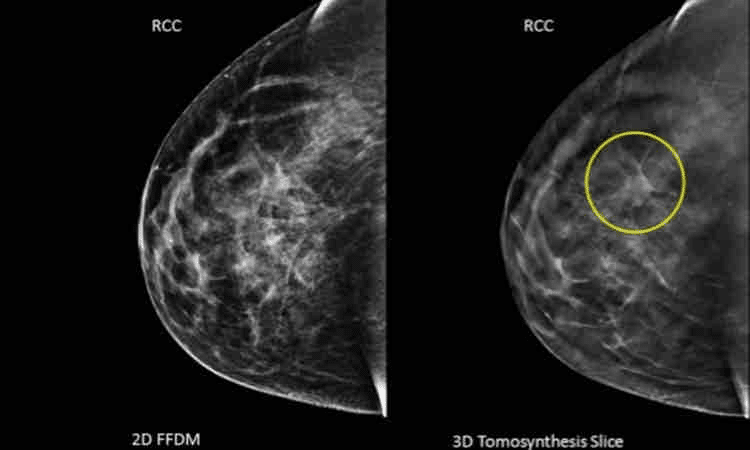

A tomossíntese, também chamada de mamografia tridimensional, é uma tecnologia avançada que complementa a mamografia convencional. Enquanto a mamografia captura imagens bidimensionais, a tomossíntese oferece cortes milimétricos que proporcionam uma visualização em 3D, reduzindo a sobreposição de tecidos. Isso é especialmente relevante em mulheres com mamas densas, onde a sensibilidade da mamografia tradicional pode ser limitada.

Um estudo coordenado por 13 hospitais universitários dos Estados Unidos publicado no “Journal of the American Medical Association” (JAMA) observou que a tomossíntese mamária, combinada a outros exames, houve um aumento de 41% na detecção de casos de câncer mais agressivos. A tecnologia de imagem 3D (à direita) possibilitou a identificação de um tumor que o método convencional não conseguiu detectar.